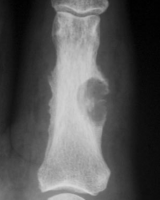

Um cisto ósseo epidermóide é uma lesão rara que ocorre quase exclusivamente nas falanges ou no crânio e se apresenta como uma lesão lítica ou um pseudotumor. Esses cistos geralmente aparecem nos pacientes, principalmente nos homens, com idades entre 25 e 50 anos. Eles são lesões benignas com evolução satisfatória após a excisão.

O cisto epidermóide é visto como uma lesão bem definida, com imagem osteolítica radiolúcida, com margem esclerótica envolvendo a falange. Estas características são bem ilustradas na mão de um adulto com cisto epidermóide nas figuras abaixo.